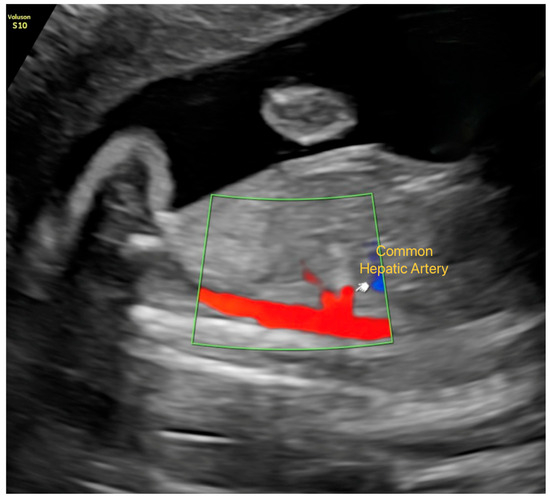

Insights into the Hepatic Arterial Buffer Response in Late-Onset FGR

by Aziz Kından, Can Ozan Ulusoy, Aykut Kından, Tuğçe Sırma, Aşkın Evren Güler, İsmail Burak Gültekin and Zehra Vural Yılmaz

Objective: To evaluate hepatic artery Doppler parameters in fetuses with fetal growth restriction (FGR) and to investigate their relationship with composite adverse neonatal outcomes (CANO). Methods: This prospective cohort study included 108 pregnancies (54 FGR; 54 appropriate-for-gestational-age controls) between 34 and 37 weeks’ [...] Read more.

Objective: To evaluate hepatic artery Doppler parameters in fetuses with fetal growth restriction (FGR) and to investigate their relationship with composite adverse neonatal outcomes (CANO). Methods: This prospective cohort study included 108 pregnancies (54 FGR; 54 appropriate-for-gestational-age controls) between 34 and 37 weeks’ gestation. Hepatic artery (HA), umbilical artery (UA), middle cerebral artery (MCA), and uterine artery Doppler indices were recorded. Logistic regression and ROC analyses were used to determine predictors of FGR and CANO. Results: HA pulsatility index (PI), systolic/diastolic ratio, and peak systolic velocity (PSV) were significantly higher in FGR fetuses (p < 0.05). In multivariate regression, HA-PI remained independently associated with FGR (aOR 1.74, 95% CI 1.07–2.87, p = 0.025). For predicting CANO, HA-PSV was the only independent predictor (aOR 1.05, 95% CI 1.00–1.10, p = 0.020). ROC analysis demonstrated moderate discriminative ability for HA-PI (AUC 0.681) and HA-PSV (AUC 0.703). Conclusions: Increased HA-PSV in FGR reflects activation of the hepatic arterial buffer response as an adaptive mechanism to maintain hepatic perfusion under hypoxic stress, whereas elevated HA-PI may represent evolving microvascular resistance. Hepatic artery Doppler evaluation may serve as a complementary tool for assessing fetal well-being and identifying fetuses at risk for adverse neonatal outcomes, particularly in late-onset FGR. Full article